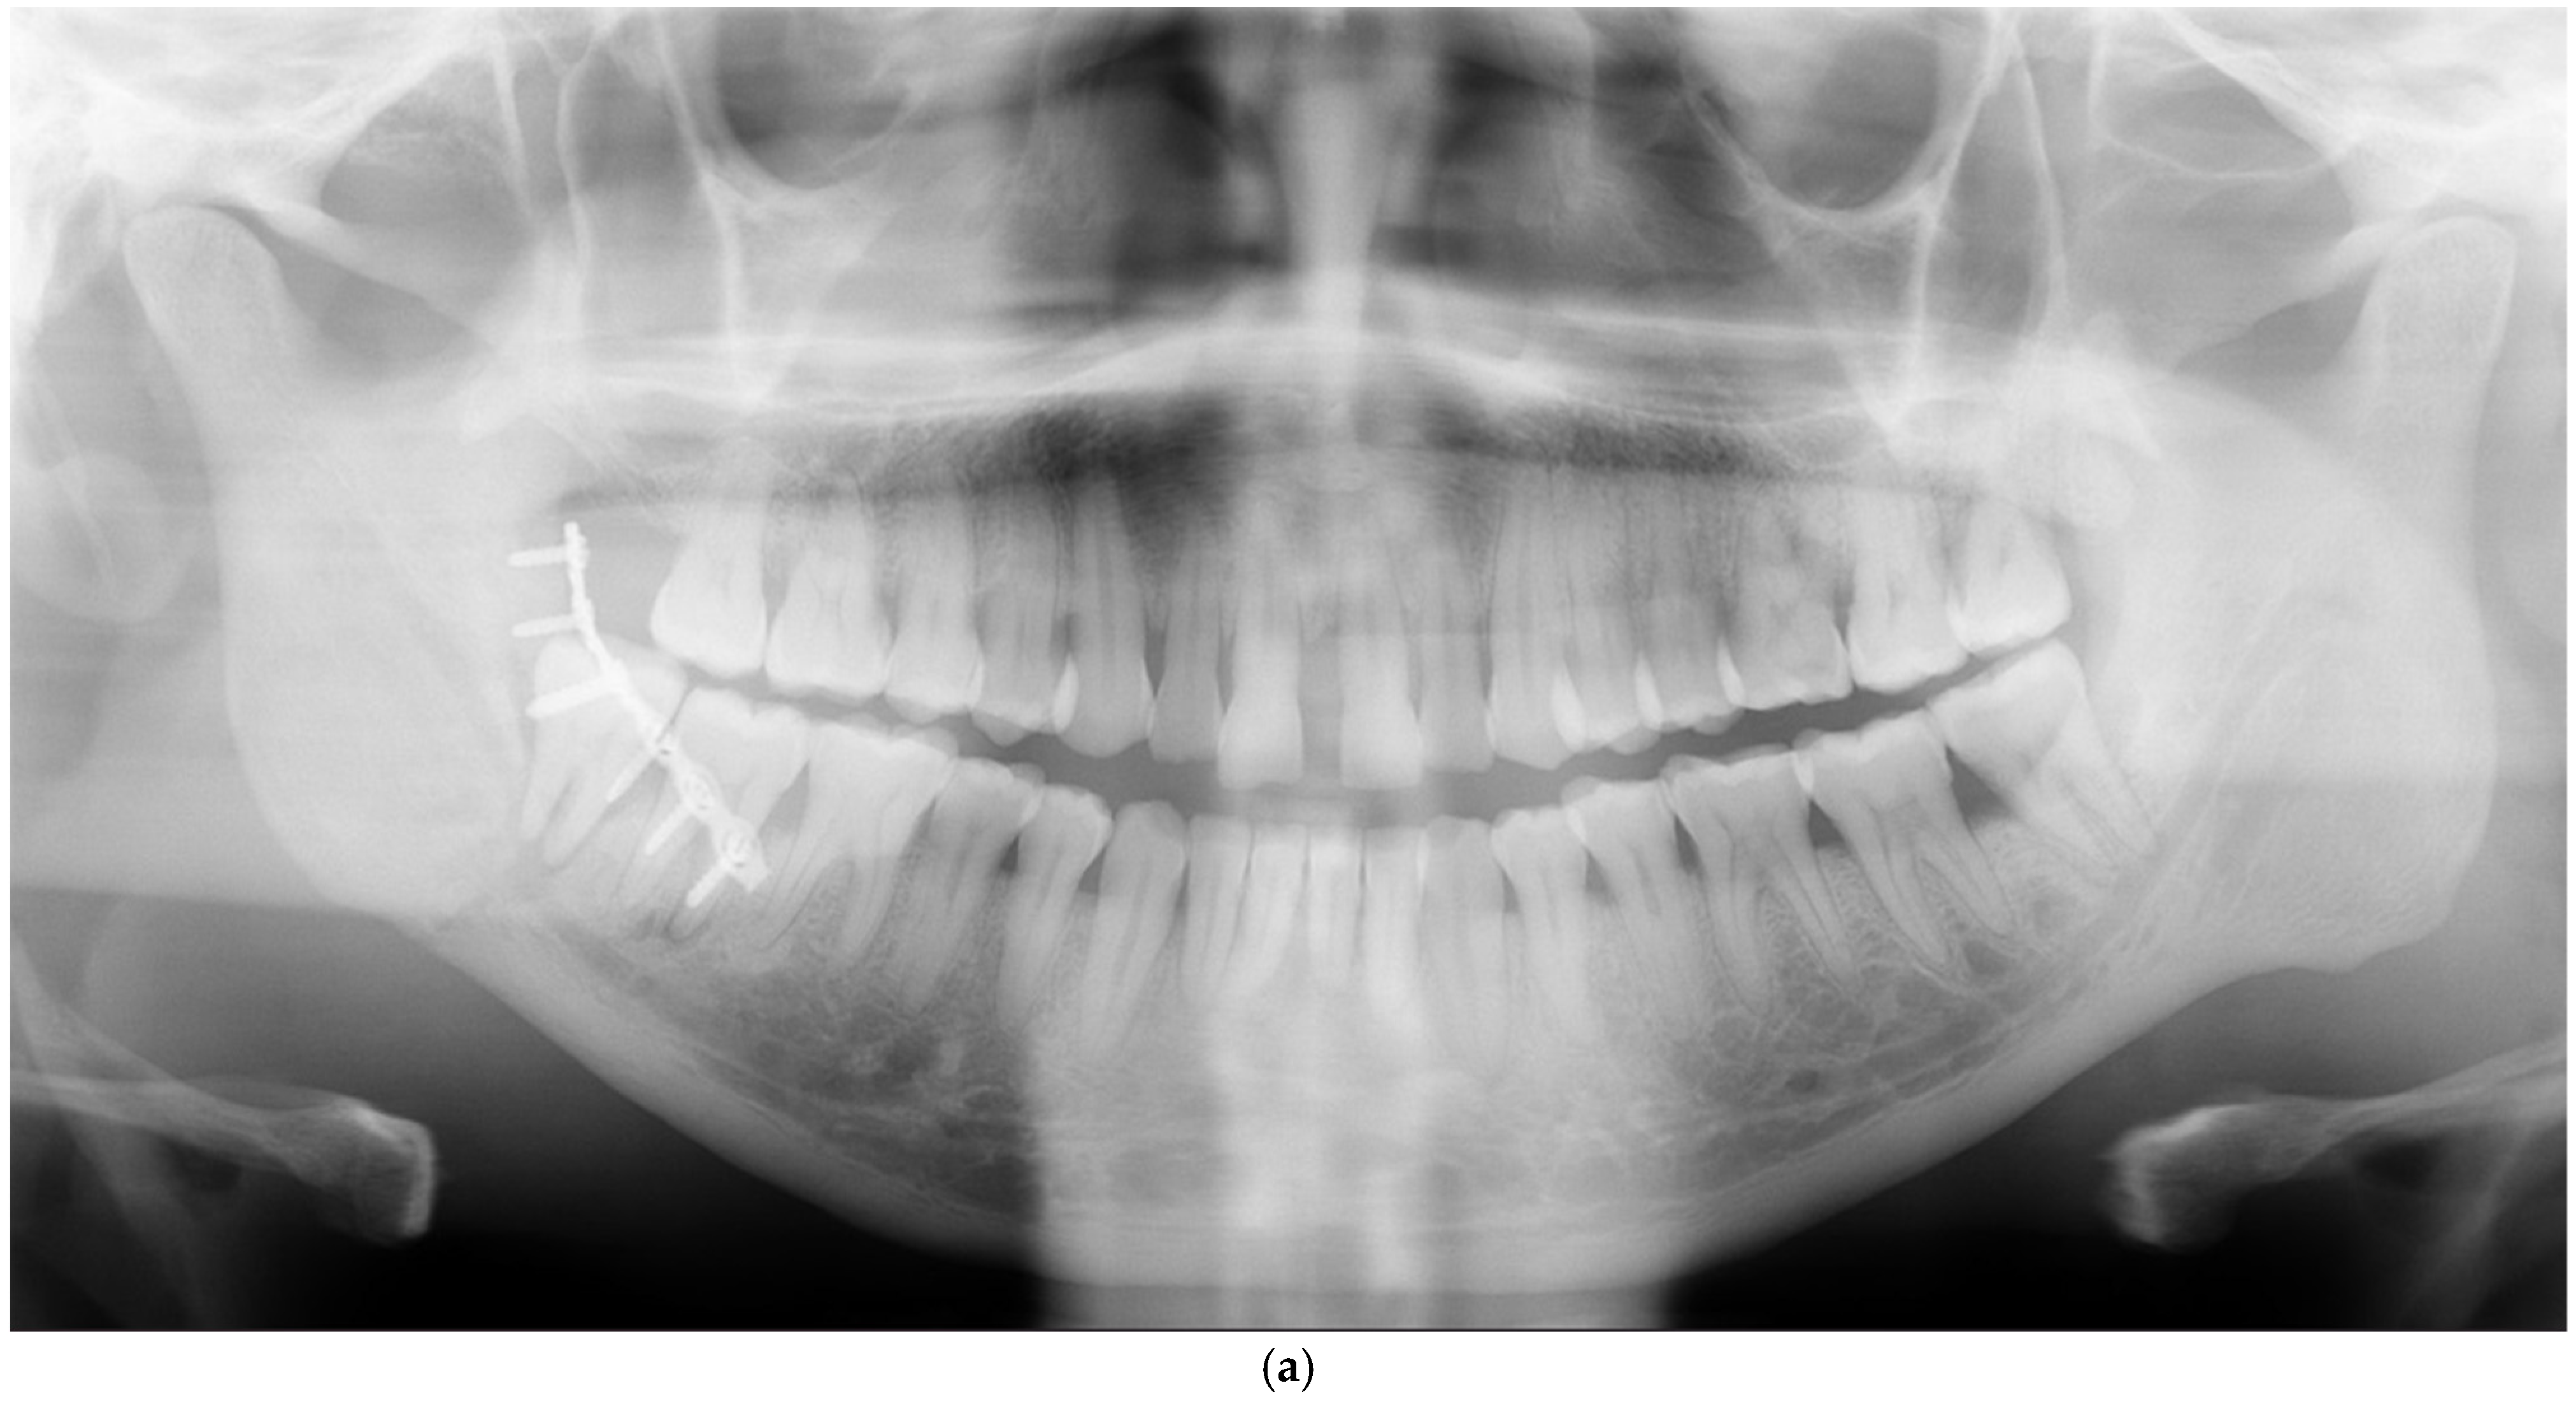

| Fractures needing redo surgery | |||||

| Mandible | 13 | ||||

| Anterior part (symphysis/parasymphysis) | 5 | 2 | 3 inadequate reductions, 2 nonunions with infection | ||

| Angle | 3 | 2 | 1 inadequate reduction, 1 infection, 1 nonunion with infection | ||

| Body | 3 | 0 | 3 inadequate reductions | ||

| Condyle | 3 | 1 | 2 inadequate reductions, 1 broken plate | ||